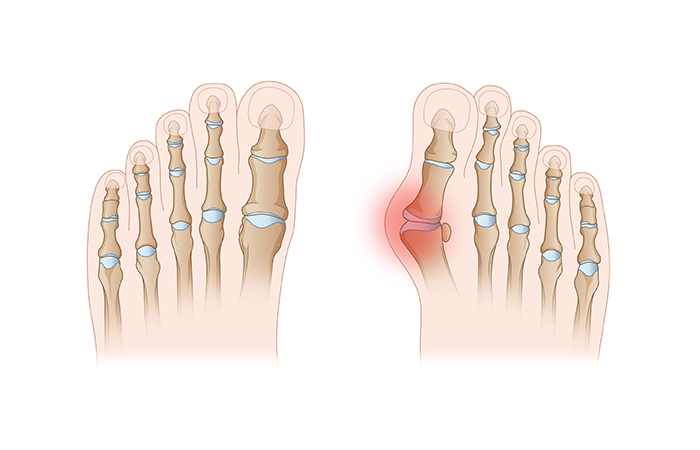

¹«Áö¿Ü¹ÝÁõ

¾öÁö¹ß°¡¶ôÀÌ ±ÙÀ§°üÀý ³»ÃøÀÌ °úµµÇÏ°Ô ÈÖ°í,

¾öÁö¹ß°¡¶ô°ú °üÀýÀ» ÀÌ·ç´Â ÁßÁ·°ñÀº

¾ÈÂÊÀ¸·Î Ä¡¿ìÄ¡´Â °üÀý º¯Çü Áúȯ

ÀÌ º¯ÇüÀº ¹ßÀÇ ¼öÆò¸é¿¡¼ÀÇ º¯ÇüÀ» ÀǹÌÇϳª ½ÇÁ¦·Î´Â ¹ß°¡¶ôÀÌ ¹ßµî ÂÊÀ¸·Î Èְųª, ¾öÁö¹ß°¡¶ô ÃàÀ» Áß½ÉÀ¸·Î ³»ÃøÀ¸·Î ȸÀüÇÏ´Â º¯ÇüÀ» µ¿¹ÝÇÑ »ïÂ÷¿øÀûÀÎ º¯ÇüÀÔ´Ï´Ù.

¹«Áö¿Ü¹ÝÁõ Áõ»ó

¾öÁö¹ß°¡¶ôÀÌ »õ³¢¹ß°¡¶ô ÂÊÀ¸·Î ÈÖ¾îÁø´Ù.

°ÉÀ» ¶§¸¶´Ù µ¹Ãâ ºÎÀ§°¡ ½Å¹ß°ú ¸Â´ê¾Æ ÅëÁõÀÌ ¹ß»ýÇÑ´Ù.

¾öÁö¹ß°¡¶ô ´ë½Å µÎ, ¼¼ ¹øÂ° ¹ß°¡¶ôÀÌ Ã¼ÁßÀ» °ßµð¸ç ±»Àº»ìÀÌ »ý±ä´Ù.

¹«Áö¿Ü¹Ý ±³Á¤¼ú

¾öÁö¹ß°¡¶ôÀÌ ÈÖ¾îÁø °¢µµ¿Í ÅëÁõÁ¤µµ¿¡ µû¶ó ¼ö¼úÀû ±³Á¤¼ú ½ÃÇà

¹ßº¼ ¾ÈÂÊÀ¸·Î Æ¢¾î³ª¿Â »À¸¦ Á¦°Å

ÈÖ¾îÁø °¢µµ¸¦ Á¤»ó¹üÀ§·Î ±³Á¤ÇÑ ÈÄ ¿¬ºÎÁ¶Á÷À» º¸°